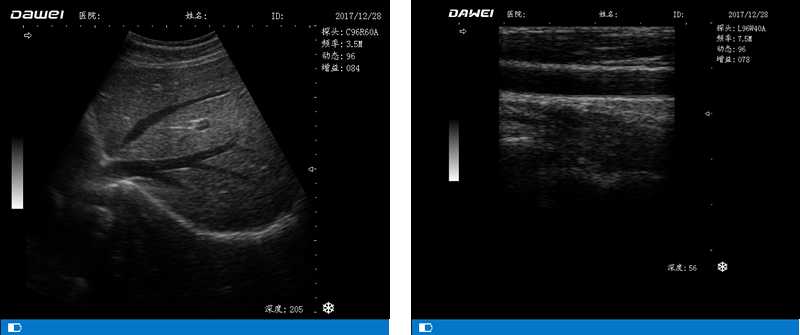

DW-500

筆記本全數字超聲診斷儀

高陣元 高清晰度 多功能

多倍率顯示 病變診斷更準確